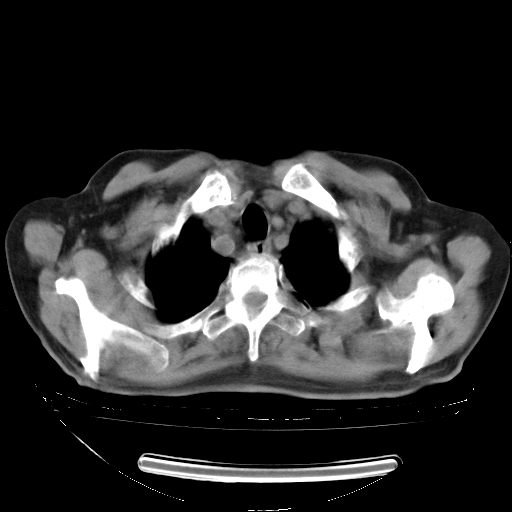

今天复查肺部CT,发现双肺广泛磨玻璃样改变。所以我把3月19日和5月9日相隔50天的肺部CT上传。请大家会诊。

2009年3月19日肺部CT片。

2009年3月19日肺部CT

胸腹部CT,诊断意见:左上肺叶钙化灶、左侧胸膜局限性增厚并钙化、胆囊炎。描述部分肺组织呈磨玻璃样改变。